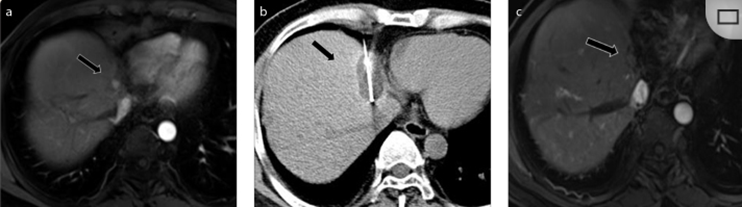

CT引導(dǎo)的冷凍消融

(a) 射頻消融后在病變邊緣顯示殘余增強(qiáng)。(b) 冷凍消融術(shù)中影像顯示冰球完全覆蓋病變。(c) 19個(gè)月后隨訪,沒有發(fā)生局部腫瘤進(jìn)展。完全消融率為97%(66/68);2名患者均接受了額外的冷凍消融,隨后實(shí)現(xiàn)完全消融。平均隨訪期為 12.8 個(gè)月(范圍:3-27 個(gè)月)。所有患者均接受影像復(fù)查(CT 或 MRI)。11個(gè)病灶(16.2%)檢測(cè)到局部腫瘤進(jìn)展,6、12和18個(gè)月時(shí)的累積局部腫瘤進(jìn)展率分別為4%、8.2%和20.5%。8例出現(xiàn)遠(yuǎn)處肝內(nèi)或肝外病變的患者接受經(jīng)動(dòng)脈化療栓塞、經(jīng)動(dòng)脈化療栓塞加射頻消融治療或全身化療。

主要和次要并發(fā)癥發(fā)生率分別為3.5%(2/57)和22.8%(13/57)。并發(fā)癥主要表現(xiàn)為局部皮膚凍傷、中度氣胸、發(fā)熱,僅有少數(shù)患者接受治療,多數(shù)患者自行恢復(fù)。所有患者能耐受圍手術(shù)期疼痛,VAS 評(píng)分范圍在 1-3 分之間(平均 1.65分)。3例患者術(shù)后疼痛加重,VAS評(píng)分達(dá)到4~5分,患者口服止痛藥后逐漸緩解。所有患者術(shù)后1天血常規(guī)、白細(xì)胞計(jì)數(shù)均升高,血小板均有不同程度下降,但變化值均在正常范圍內(nèi)。肝功能1個(gè)月后逐漸恢復(fù)到正常水平。